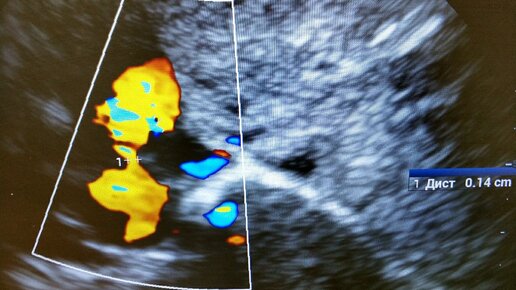

Открытое овальное окно (ооо, фоо) и дефекты мпп

Что за зверь ФОО? Открытые овальные окна или дефекты перегородок? Настоящий кошмар молодых мам и холивар специалистов диагностики. Открытое овальное окно это шунт, который существует внутриутробно, пока малыш в животе мамы. Благодаря особенности роста первичной и вторичной межпредсердной перегородки, образуется "клапан" напоминающий ветряной носок, или ласту. Пока давление в правых отделах высокое, лёгкие не раскрыты, шунт активно работает. После рождения лёгкие раскрываются, в первые несколько дней градиент давления лево/право растет, "клапан" закрывается...